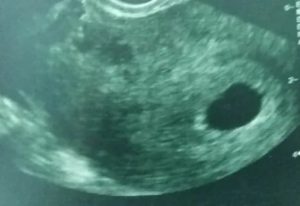

Так на УЗИ выглядит пустое плодное яйцо.

Пустое плодное яйцо – это по сути беременность, которая не начала развиваться. Процесс развития прекратился еще до этапа формирования эмбриона. Причин такого нарушения достаточно много.

При постановке диагноза анэмбриония следует немедленно принять необходимые меры, так как это влечет за собой неизбежную гибель плода.

Только на шестой неделе беременности пустое плодное яйцо можно диагностировать с помощью УЗИ. Оно проводится в любом случае, чтобы определить месторасположение плода, а также исключить внематочную беременность.